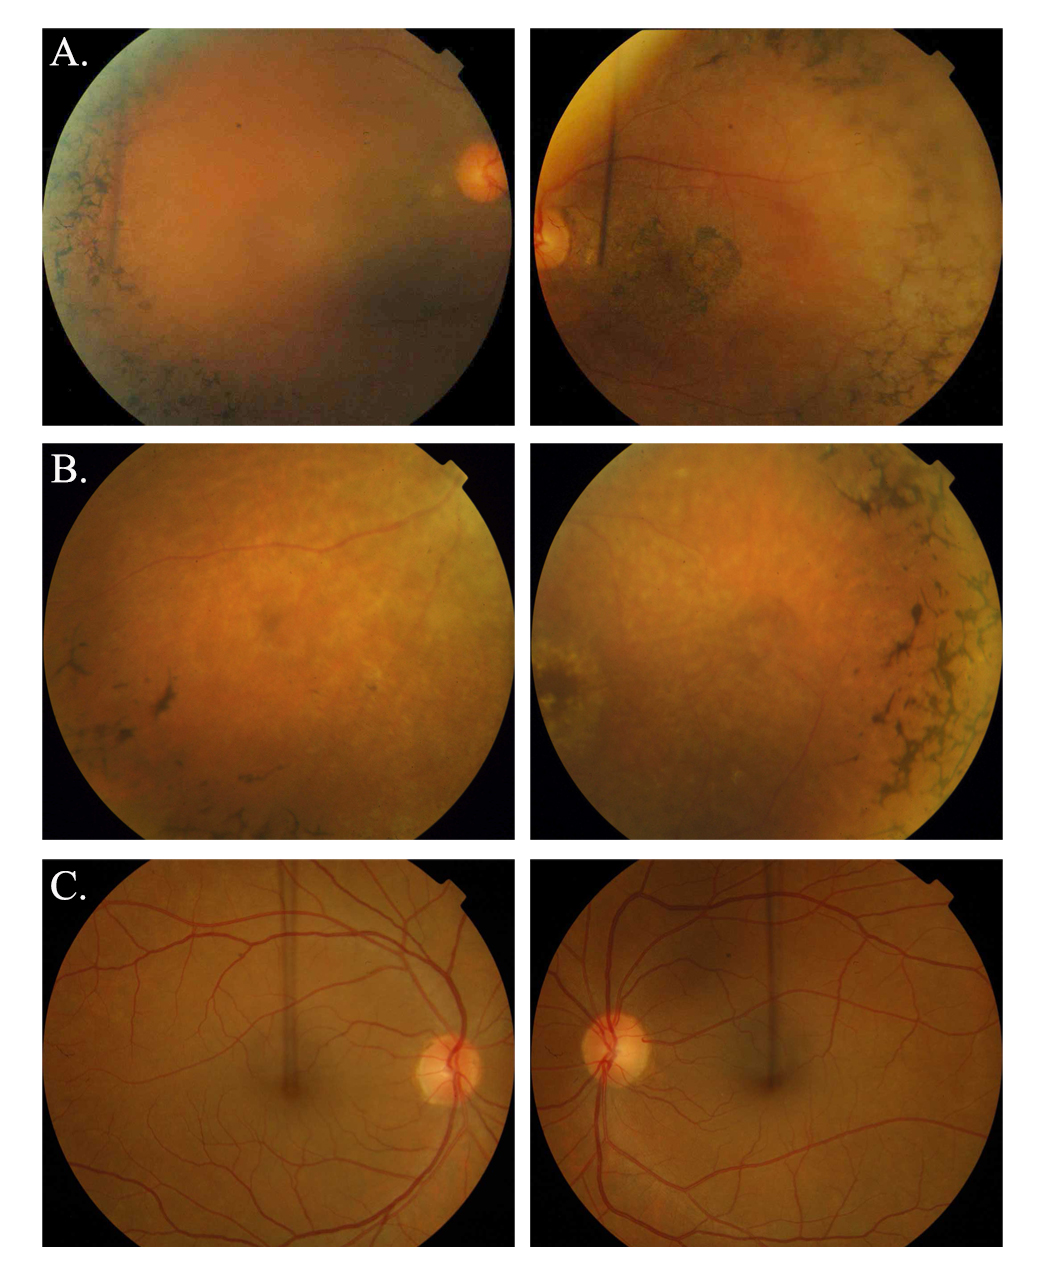

Figure 2. Fundus photographs of affected individuals illustrating symptoms of retinitis pigmentosa. A: OD and OS of individual 10 (affected: 30 years) of family PKRP259. B: OD and OS of individual 11 (affected: 18 years) of family PKRP309. C: OD and OS of individual 8 (unaffected: 52 years) of family PKRP259. Fundus photographs of affected individuals show bone

spicule-like pigmentation in the mid-periphery of the retina, attenuated retinal arterioles, severe maculopathy, and disc

pallor. OD = oculus dexter; OS = oculus sinister.